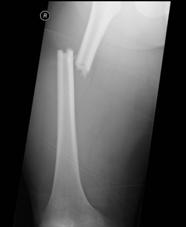

Fracturi simple: SPIRALA OBLICA TRANSVERSALA

Fractura spirala de Fractura transversa de diafiza femurala Fractura spirala de diafiza tibiala

diafiza humerala

Fractura spirala de diafiza tibiala Fractura oblica de diafiza tibiala Fractura transversala de diafiza tibiala